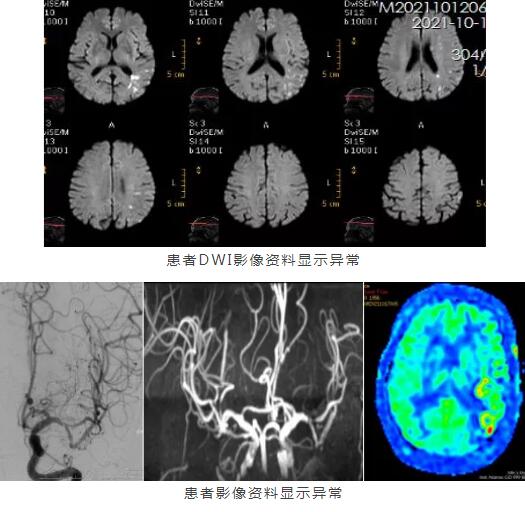

患者到达医院后,王展航立即对他进行评估,又迅速为患者安排相关检查。根据检查结果,王展航明确患者是脑梗死。该病的最佳治疗时间是发病起的4.5小时内,患者起病时间仍在静脉溶栓时间窗。在与家属沟通并取得同意后,立即为患者进行静脉溶栓。

时间就是生命,每早一分钟溶栓,可减少200万神经细胞的死亡,大大降低终身残疾的可能。入院半小时,救命的溶栓药已经进入了林伯的体内。但进一步检查后,王展航发现患者左侧大脑中动脉重度狭窄,加上患者语言表达困难的问题仍十分严重,且存在下肢乏力的情况,邀请神经介入科主任王培明会诊后,一致认为患者需接受进一步介入治疗。

经过多学科通力合作,成功为患者实施左侧M1段重度狭窄球扩成形+支架植入术。经过及时的静脉溶栓联合血管内介入治疗,林伯终于能与家属对答如流了,双下肢也能自主活动。